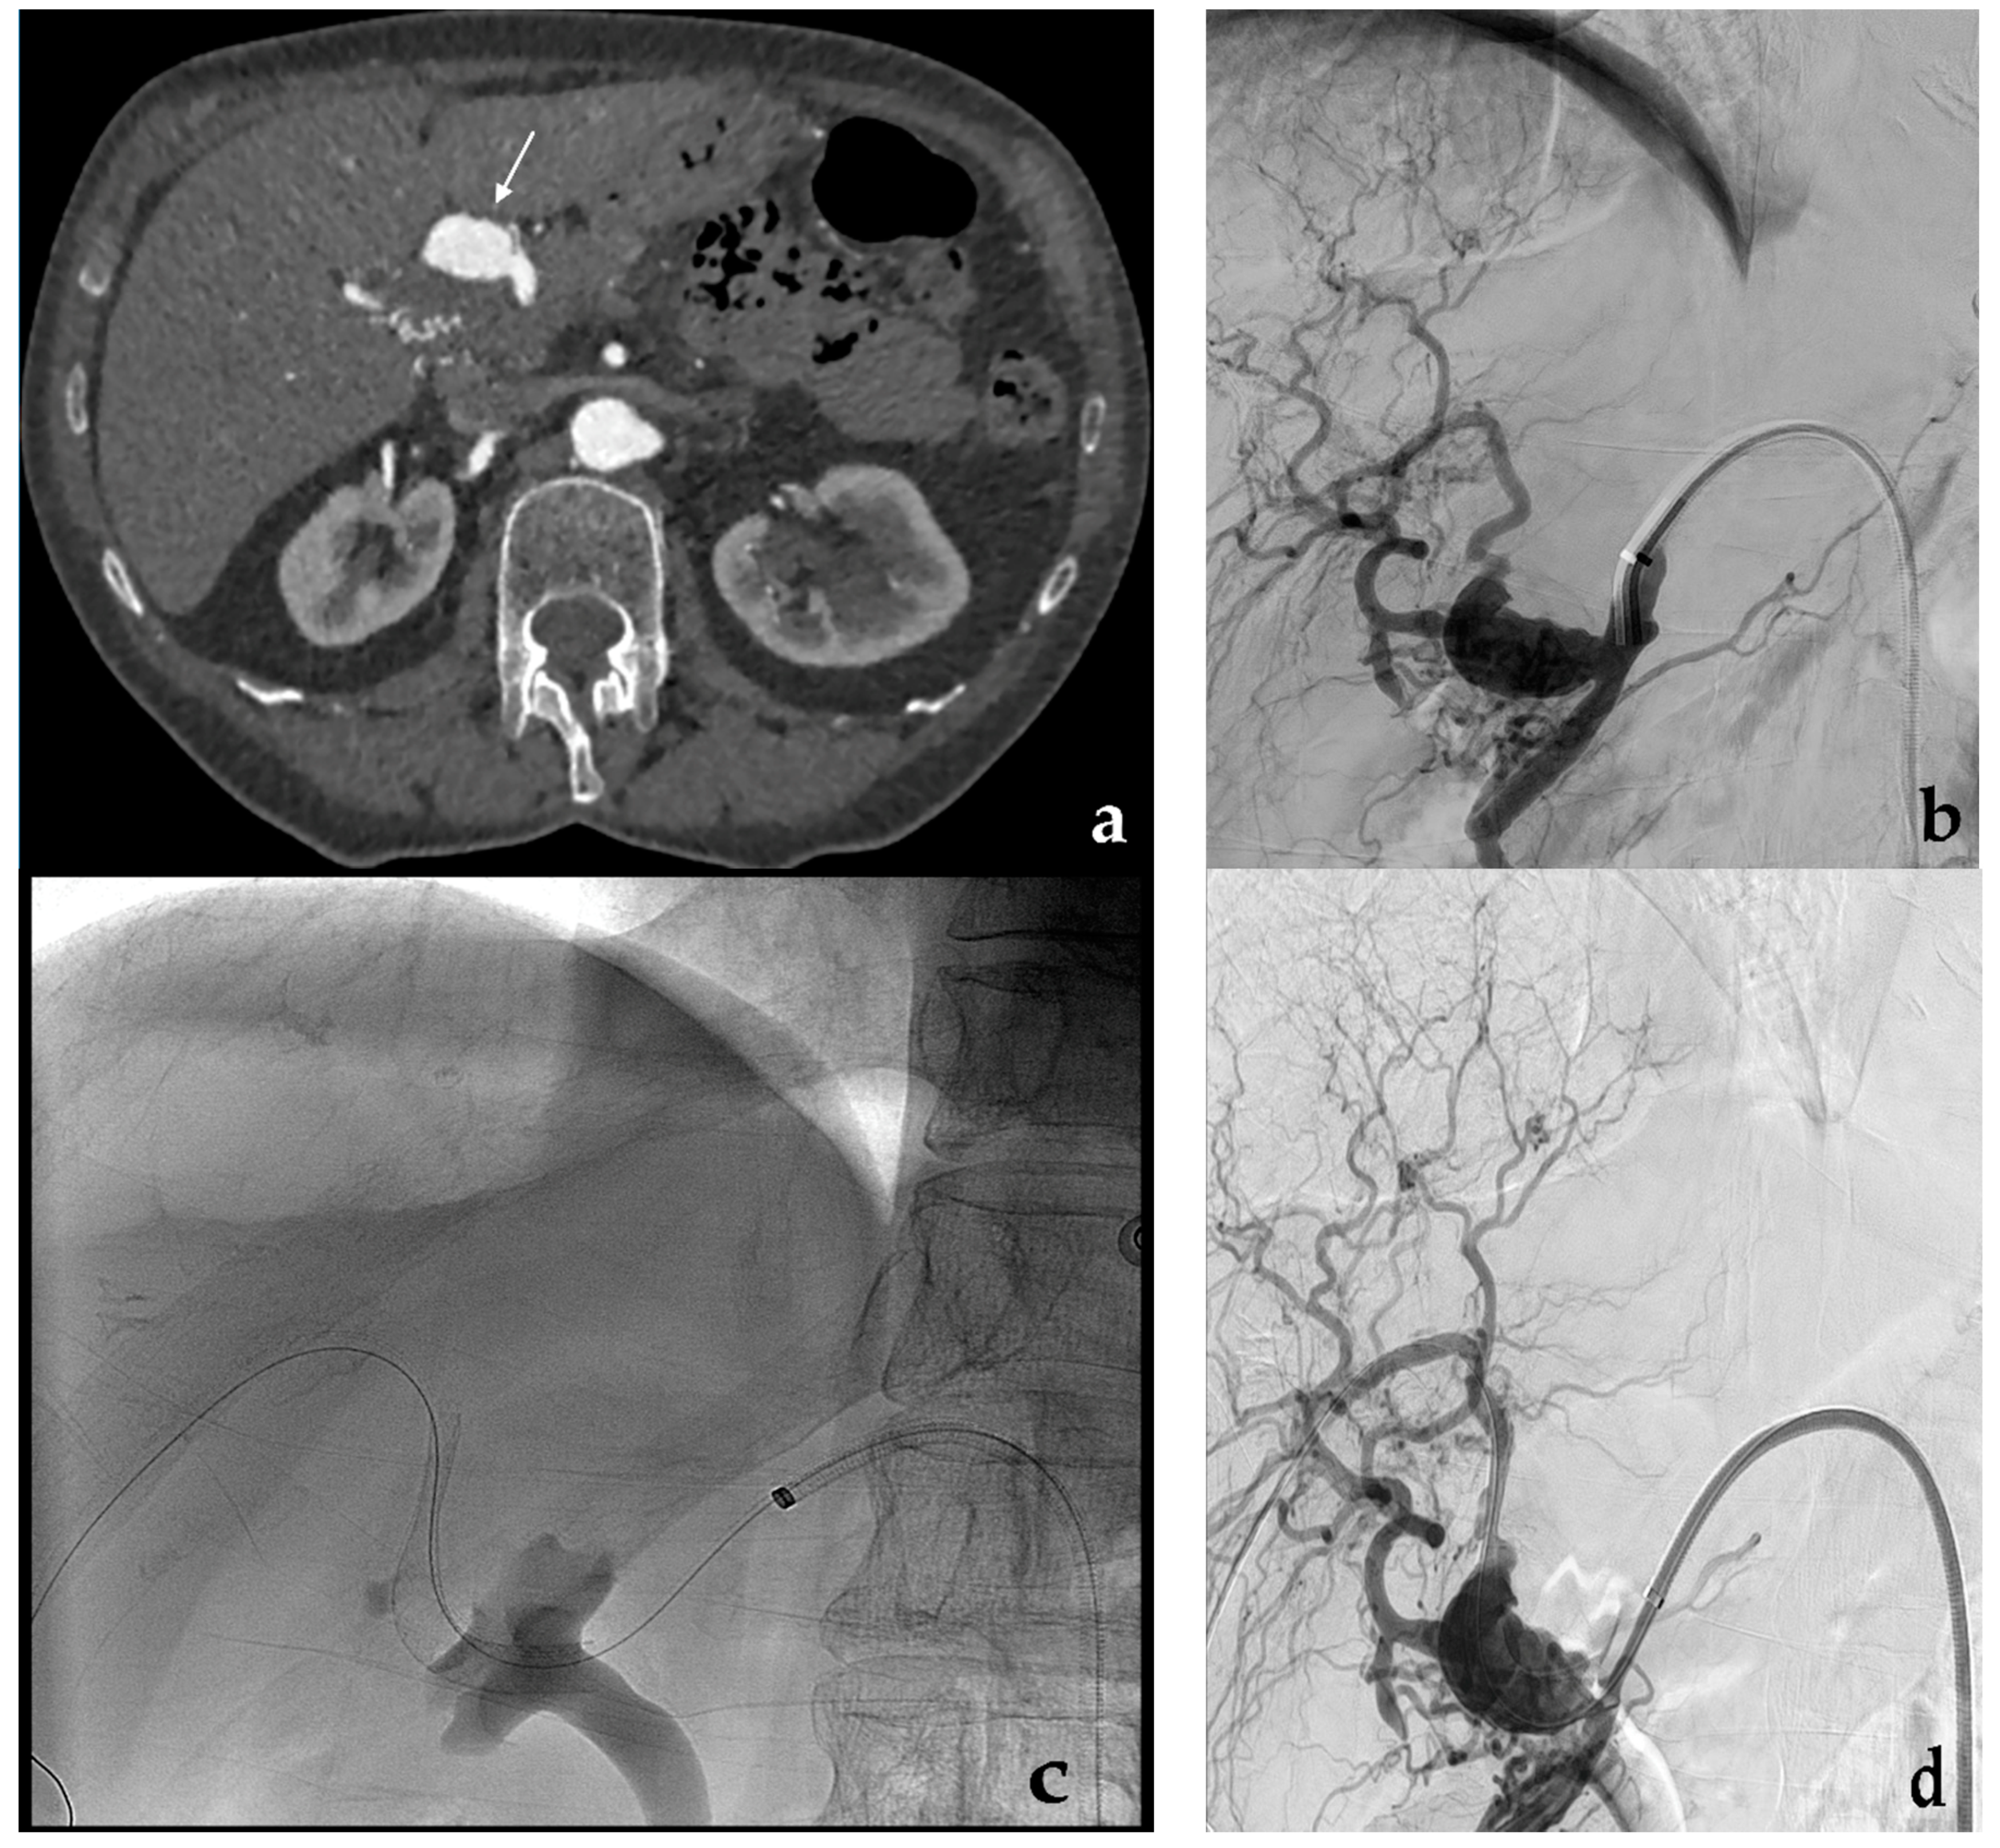

- Venturini, M.; Della Corte, A.; Lanza, C.; Fontana, F.; Chiesa, R.; De Cobelli, F. Embolization of 2 coexisting intraparenchymal renal artery aneurysms with an ethylene vinyl alcohol copolymer agent (Squid) and coils. Cardiovasc. Interv. Radiol. 2020, 43, 942–944. [Google Scholar] [CrossRef] [PubMed]